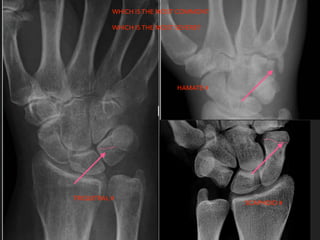

WHICH IS THE MOST COMMON?

WHICH IS THE MOST SEVERE?

TRIQUITRAL # HAMATE # SCAPHOID# WHICH IS THE MOST COMMON? WHICH IS THE MOST SEVERE?